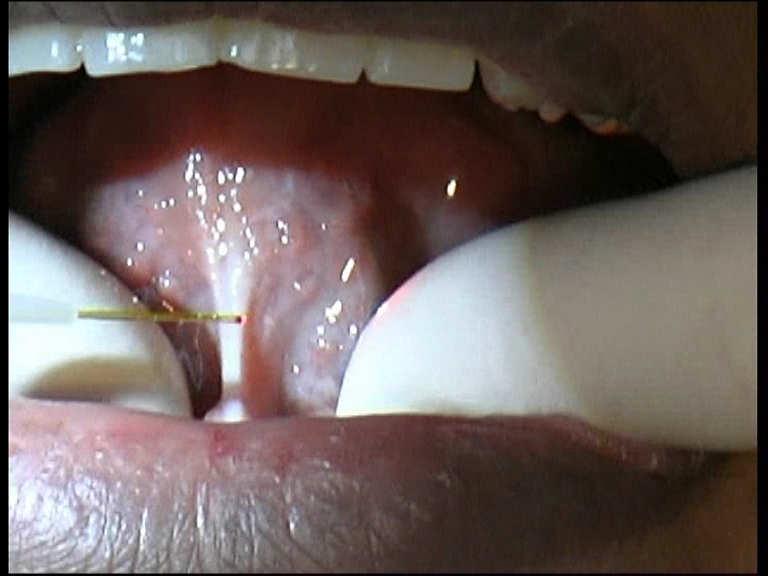

Diode Laser 810nm

Power: 2.5 Watt,

Pulsed 50 Hz

Fibre 400 micron

Mucogingival Surgery